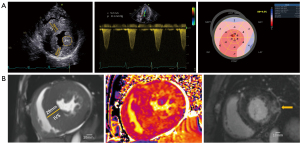

CMR imaging showed severe LVH in all four patients. Patients 1 and 2 exhibited decreased native myocardial T1 values, whereas Patients 3 and 4 had elevated T1 values (Table 1). A basal inferolateral pattern of LGE was noted in Patients 3 and 4 (Figure 1). The native T1 values measured in the LGE regions were 1,493 and 1,386 ms in Patients 3 and 4, respectively, significantly higher than the normal range established at our institution (1,240–1,300 ms).

Guided by TEE, all surgeries were successfully performed, resulting in immediate hemodynamic improvements (Figure 2). None of the patients required blood transfusion, and no major complications or adverse events—such as permanent complete heart block, iatrogenic ventricular septal perforation, valvular injury, or cerebrovascular events—were observed. The postoperative course was uneventful, with all patients discharged in stable condition on postoperative day 7.

Mean septal thickness decreased from 26.0±4.1 mm preoperatively to 18.0±3.9 mm. Maximal instantaneous LVOT gradients were significantly reduced, from 111.0±44.3 mmHg preoperatively to 26.5±8.3 mmHg postoperatively, demonstrating effective relief of LVOT obstruction. All patients with preexisting MR (≥3+) and systolic SAM (≥2) exhibited notable improvements, with MR grade reduced to ≤2+ and SAM grade reduced to ≤1. Left ventricular GLS improved slightly from 6.6%±3.0% to 9.5%±2.3% (absolute values) on postoperative assessments (Figure 4). Additionally, left ventricular stroke volume, as a surrogate for myocardial contractility, improved significantly in all patients.